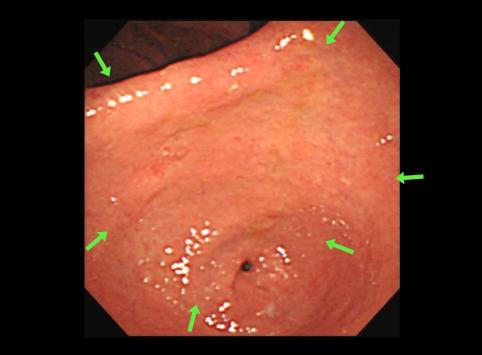

疾患(病理主体)の分類悪性上皮性腫瘍/腺癌

部位(臓器別)胃(部位)/2つ以上

検査方法内視鏡

腫瘍の肉眼分類0型(表在型)/IIc型(IIc+IIb)

病変の最大径(ミリ)40以上

腫瘍の深達度m